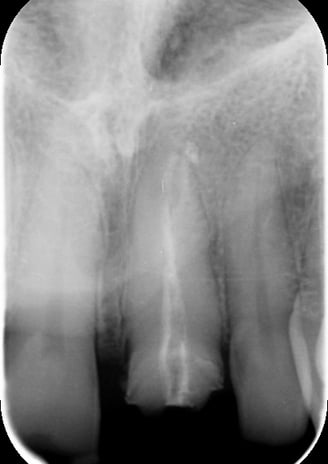

1. Ritrattamento Endodontico

Il primo step è stato il ritrattamento endodontico, essenziale per garantire la salute a lungo termine del dente. Dopo la rimozione della vecchia otturazione canalare, è stata effettuata una detersione accurata con irriganti specifici e successiva otturazione tridimensionale per prevenire recidive infettive.

Trattamento Canalare Congruo